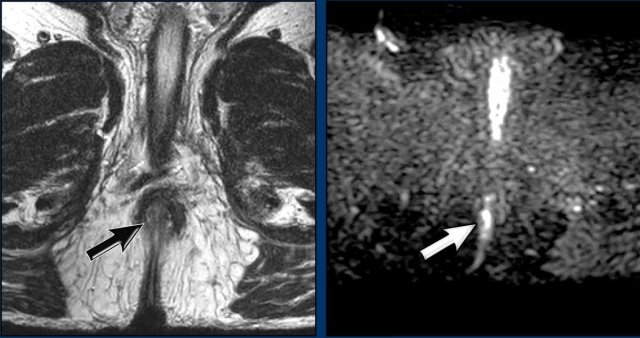

Evaluation after 6 weeks

The first response evaluation was performed 6 weeks after the last radiation fraction.

Images

There is response, but residual tumor is still visible as intermediate signal tissue on T2W MRI (black arrow) with corresponding diffusion restriction (white arrow).

Continue with the follow up at 6 months...

Evaluation after 6 months

A second response evaluation was performed at 6 months post-radiation.

There is a complete response.